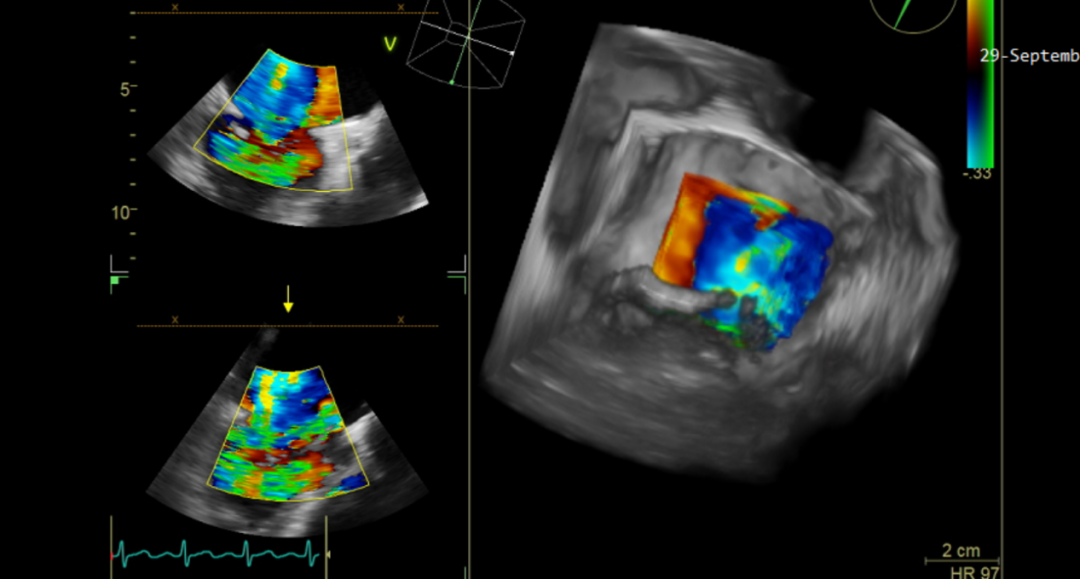

70岁的王奶奶患心脏病多年, 10+月胸闷、气促、心悸不适,加重5天,上述症状反复发作,4+前患者症状加重,表现安静休息时亦发作,活动耐量下降,尿量明显减少,就诊于我院行TTE示“二尖瓣脱垂,重度反流,三尖瓣重度反流,肺动脉高压”,调药3月余遂至我院复查超声,行TEE示“二尖瓣后叶P3区明显脱垂并腱索断裂,重度反流,三尖瓣中度反流,脱垂宽度6.9mm,脱垂深度6.3mm,反流颈宽度6.1mm”。(图2)

图2 患者二:TEE提示二尖瓣重度反流,P3区,腱索断裂